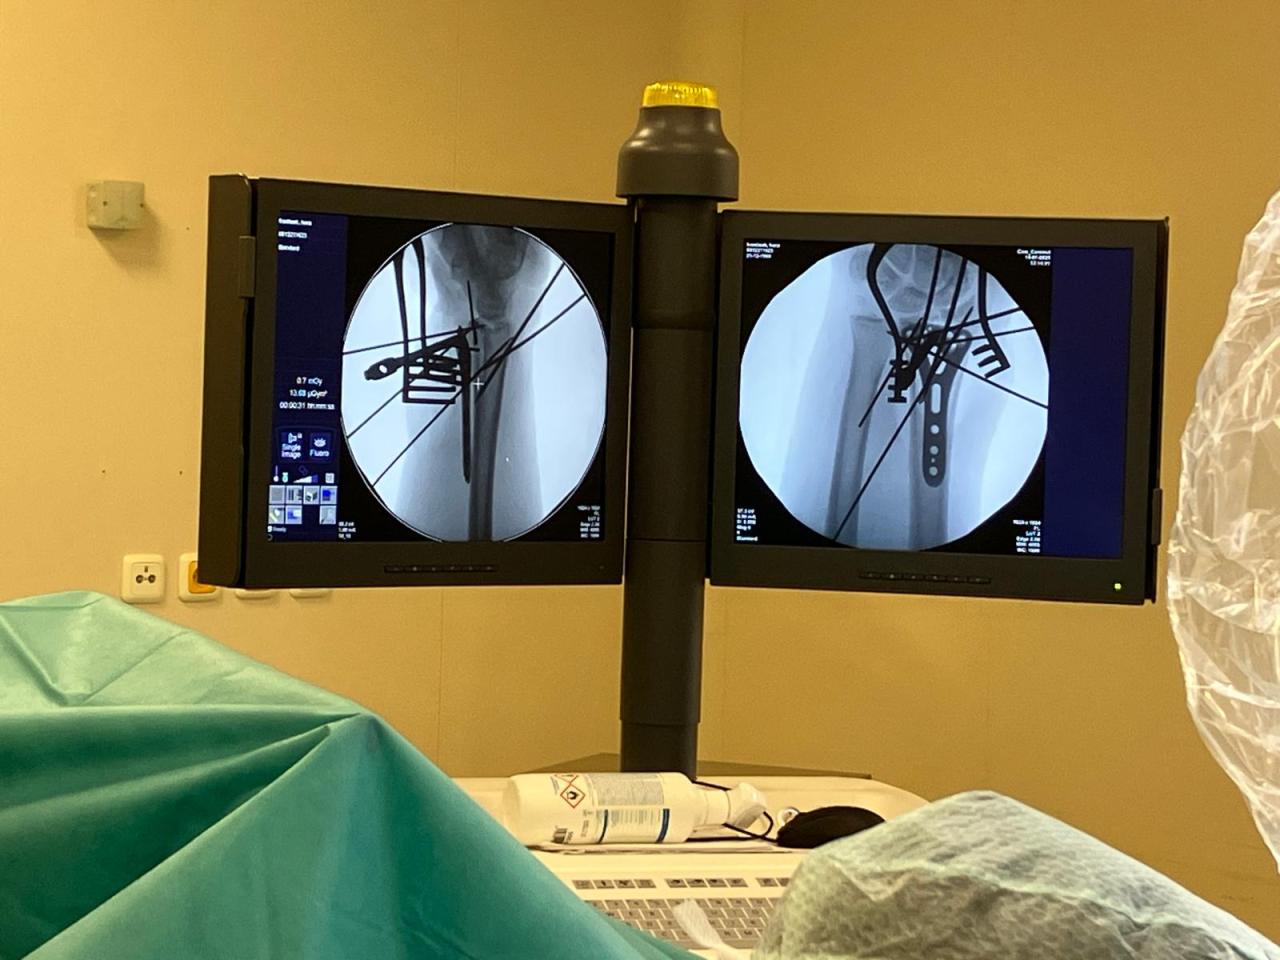

Moderní vybavení, šikovné ruce zkušených chirurgů, anesteziologové, spolehlivé sestry i další zdravotníci... To je dokonalá souhra, která je potřeba k úspěšně provedenému chirurgickému zákroku.

V čáslavské nemocnici podstupuje operační zákroky několik pacientů denně. Zajímá vás, jak to při takové operaci vypadá? Podívejte se na pár zajímavých záběrů z operačního sálu.